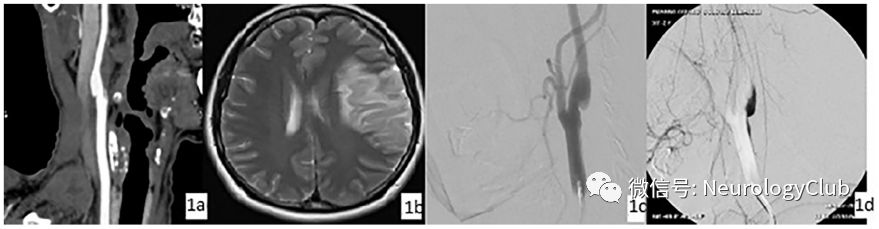

(图2:a:CT血管造影提示可能的颈内动脉蹼;b:MRI可见左侧额颞区缺血性病变;c-d:DSA证实颈内动脉蹼;引自:Pacei F, Quilici L, Mullin S, Innocenti A, Valvassori L, Nardone R, Bet L.Web of the carotid artery: An under-recognized cause of ischemic stroke.J Clin Neurosci. 2018 Apr;50:122-123.)